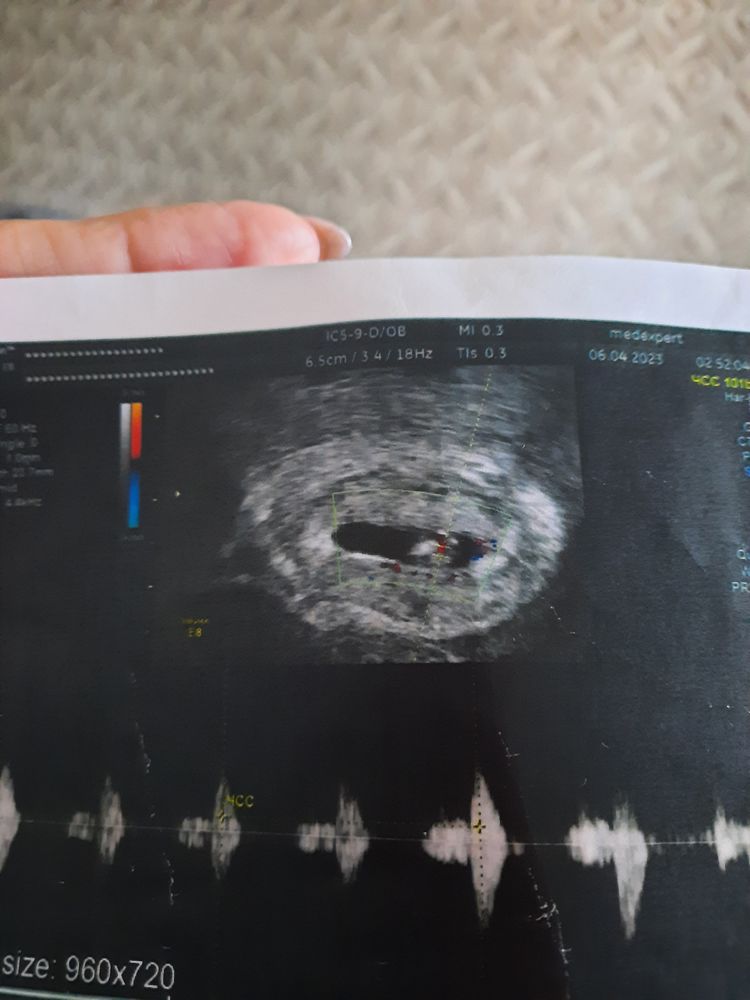

Изображение В этот раз по Рамзи у нас должна была быть дочка Изображение Фото по животу, значит зеркалим и будет как у вас хорион вверху.

Мария, я тут нашла ещё УЗИ с сыном , там вроде с другой стороны?) )  Изображение